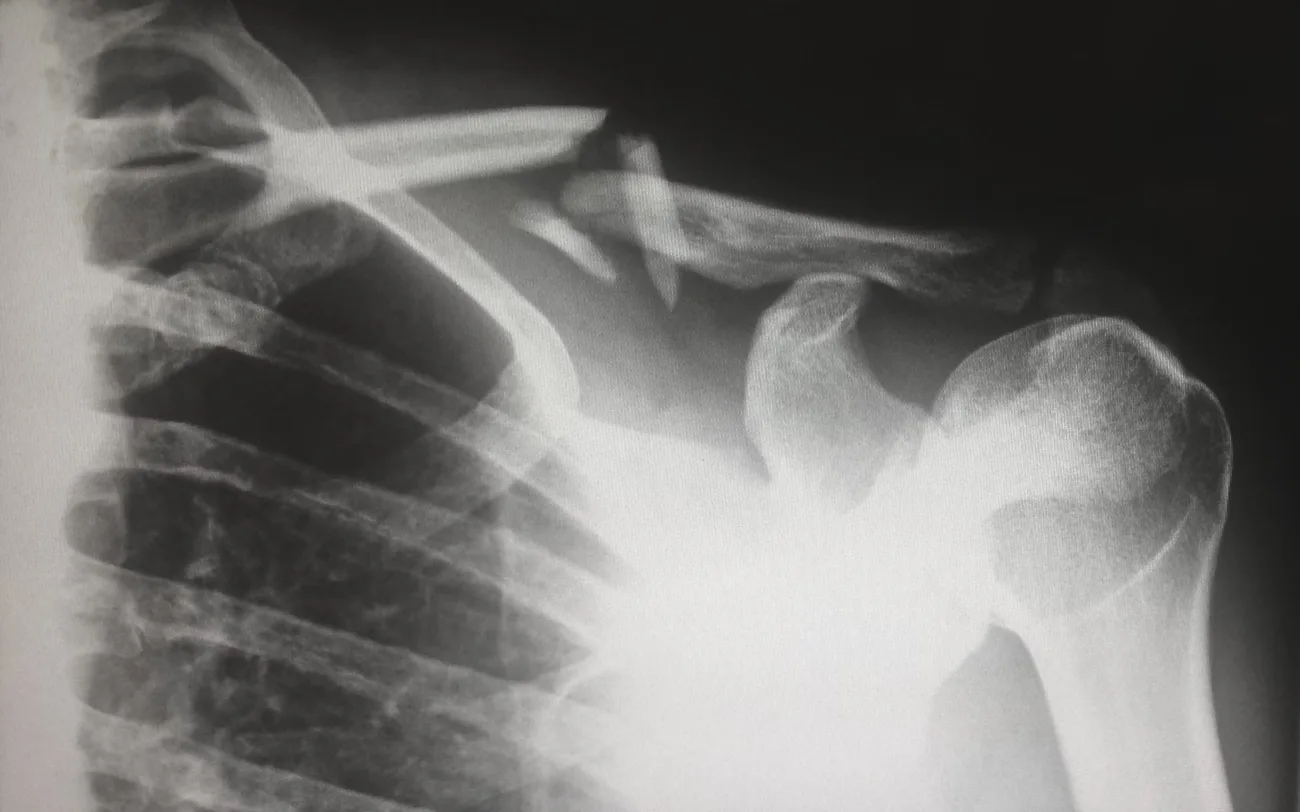

Your health should be your primary concern immediately after an injury. Seek medical attention even if your injuries seem minor. Delayed symptoms can arise, particularly with injuries like concussions or fractures. Follow your doctor’s treatment plan closely, which might include medication, physical therapy, or follow-up appointments.

Becoming familiar with your rights can empower you to take the necessary steps after your injury. In many cases, you are entitled to compensation for medical expenses, lost wages, and pain and suffering. Thus, thorough documentation is vital when it comes to protecting your legal rights. Keep a detailed account of your injuries, medical visits, treatment plans, and any related expenses. Take photographs of your injuries and maintain copies of all medical reports, bills, and correspondence with insurance companies. This information can be instrumental if you later decide to file a claim, as it provides tangible evidence of your situation.